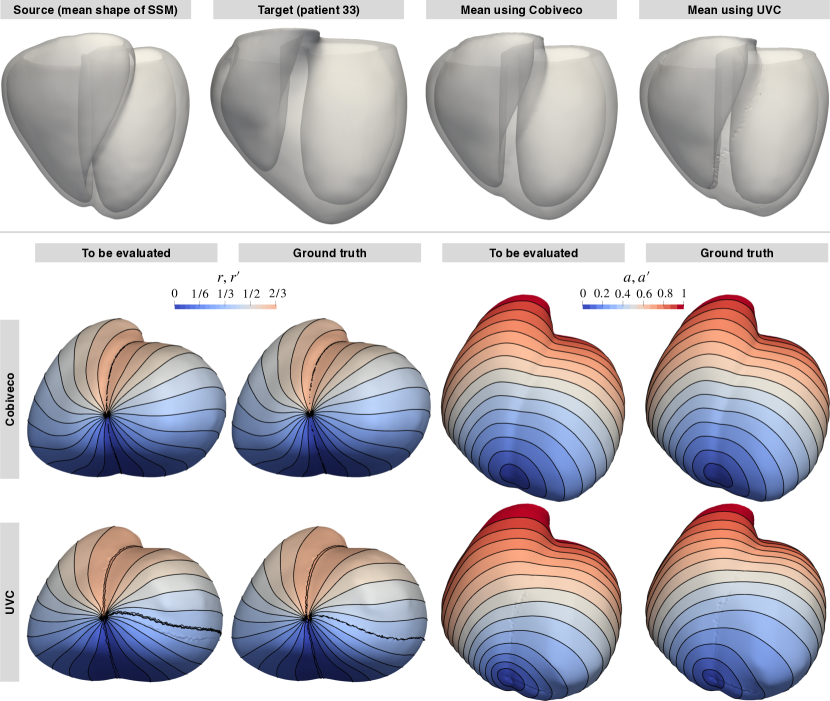

4.2 Visual comparison

Fig. 14 provides a visual comparison of Cobiveco and UVC for all four coordinates on the mean shape of the SSM and two exemplary patient geometries.

As the mean shape has a very uniform wall thickness, the contour lines of the rotational and apicobasal coordinates appear equidistant for both methods, but artifacts at the discontinuities of the rotational coordinate can be seen for UVC (green circles).

Patient 36 also has a relatively uniform wall thickness, but differences between both methods become more apparent. For UVC, the distance between contour lines of the rotational coordinate increases near the septal junctions (magenta vs. cyan circle), which is not the case for Cobiveco.

In patient 33, the differences are most pronounced. While the coordinates computed using Cobiveco still change very uniformly in space, there are substantial distortions in the UVC coordinates. The length of the segments between contour lines of the rotational coordinate changes up to four-fold between regions of small and large wall thickness. The apicobasal coordinate is also distributed very non-uniformly, indicating that the geodesic approach to normalize the apicobasal Laplace solution does not work reliably. In fact, a slight change of the geometry can cause a different geodesic path between apex and base to become the shortest and therefore lead to an abrupt change of the apicobasal coordinate. Taking a closer look at the transmural coordinate within the LV shows that it changes much faster at the endocardium than it does at the epicardium because the width of the region between the two boundary surfaces increases with the circumference.

If the coordinates always showed the same distortions for every geometry, this would only be a minor problem. However, comparing the rotational and apicobasal UVC coordinates for patient 33 and the mean shape reveals that the same coordinate values can represent quite different anatomical regions (yellow stars). In contrast, the coordinates obtained using Cobiveco are consistent across the geometries (green stars).

For pictures showing Cobiveco and UVC coordinates on all 36 patient geometries, the reader is referred to Fig. S1 and S2, respectively.